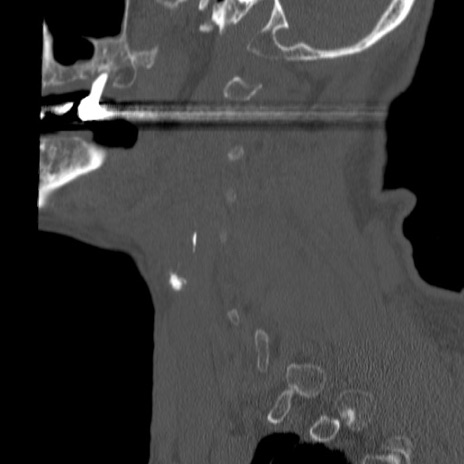

症例46 頚椎CT(矢状断像)

【症例】80歳代男性

【主訴】両側頚部〜上肢のしびれ

【現病歴】昨日、自宅内で転倒、その後より上記症状あり。意識障害なし。

【身体所見】両側上肢のallodynia(熱痛覚過敏)あり。MMTおよびDTRは正確な所見取れず。両上肢の挙上はなんとか可能。

異常所見と診断は?